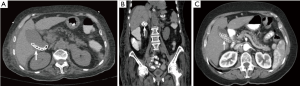

A 73-year-old female with a history of primary biliary cirrhosis, Sjogren syndrome, and hypertension recently presented with nausea, vomiting, and fever. She was found to have panhypopituitary syndrome, and extensive mediastinal and retroperitoneal lymphadenopathy. A lymph node biopsy revealed diffuse large B-cell lymphoma. A CT scan without contrast of the abdomen in January 2015 revealed cholelithiasis but no biliary dilation or gallbladder wall edema (arrows in panel A, horizontal view; and panel B, coronal view). There was no significant abnormality in her liver function tests. A prior CT scan with contrast of the abdomen done in September 2004 also showed cholelithiasis with no biliary dilation (arrow in panel C). Even though the gall bladder was filled with stones over the past 10 years, the patient remained asymptomatic and needed no intervention for the extensive cholelithiasis. This case shows the natural history of extensive incidental cholelithiasis over at least 10 years.